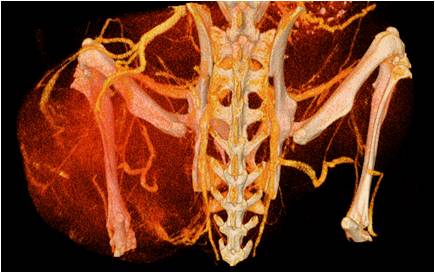

胸部和心血管的層析成像 胸部和心血管的3D圖像

心血管.jpg 心血管1.jpg